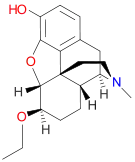

Codeine-dionine family

- 6-Monoacetylcodeine

- Benzylmorphine

- Codeine methylbromide

- Desocodeine

- Dimethylmorphine (6-O-Methylcodeine)

- Ethyldihydromorphine

- Methyldihydromorphine (dihydroheterocodeine)

- Ethylmorphine (dionine)

- Heterocodeine

- Isocodeine

- Pholcodine (morpholinylethylmorphine)

- Myrophine

- Thebacon

- Transisocodeine

Structures

| Codeine-dionine family | ||||

|---|---|---|---|---|

6-Monoacetylcodeine 6-Monoacetylcodeine |

Benzylmorphine Benzylmorphine |

Codeine methylbromide Codeine methylbromide |

Desocodeine Desocodeine |

Dimethylmorphine Dimethylmorphine(6-O-Methylcodeine) |

Ethyldihydromorphine Ethyldihydromorphine |

Methyldihydromorphine Methyldihydromorphine(dihydroheterocodeine) |

Ethylmorphine Ethylmorphine |

Heterocodeine Heterocodeine |

Isocodeine Isocodeine |

Pholcodine Pholcodine |

Myrophine Myrophine |

Transisocodeine Transisocodeine | ||